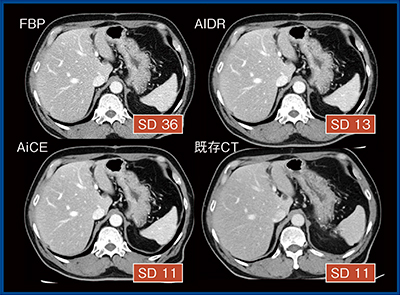

FBPでは,ファントム形状の変化(1:1→1:1.25)によって画像SD値が上昇するのに比べて,AiCE,AIDR 3Dではほぼ一定となっている。管電流200mA,スライス厚5mmの場合,FBPではSD値35だが,AiCEでは10程度となる。さらに,0.5mmのthin slice画像では,AiCEによってより高いノイズ低減効果が期待できる(図3)。

図3 ファントム位置と画像SD値